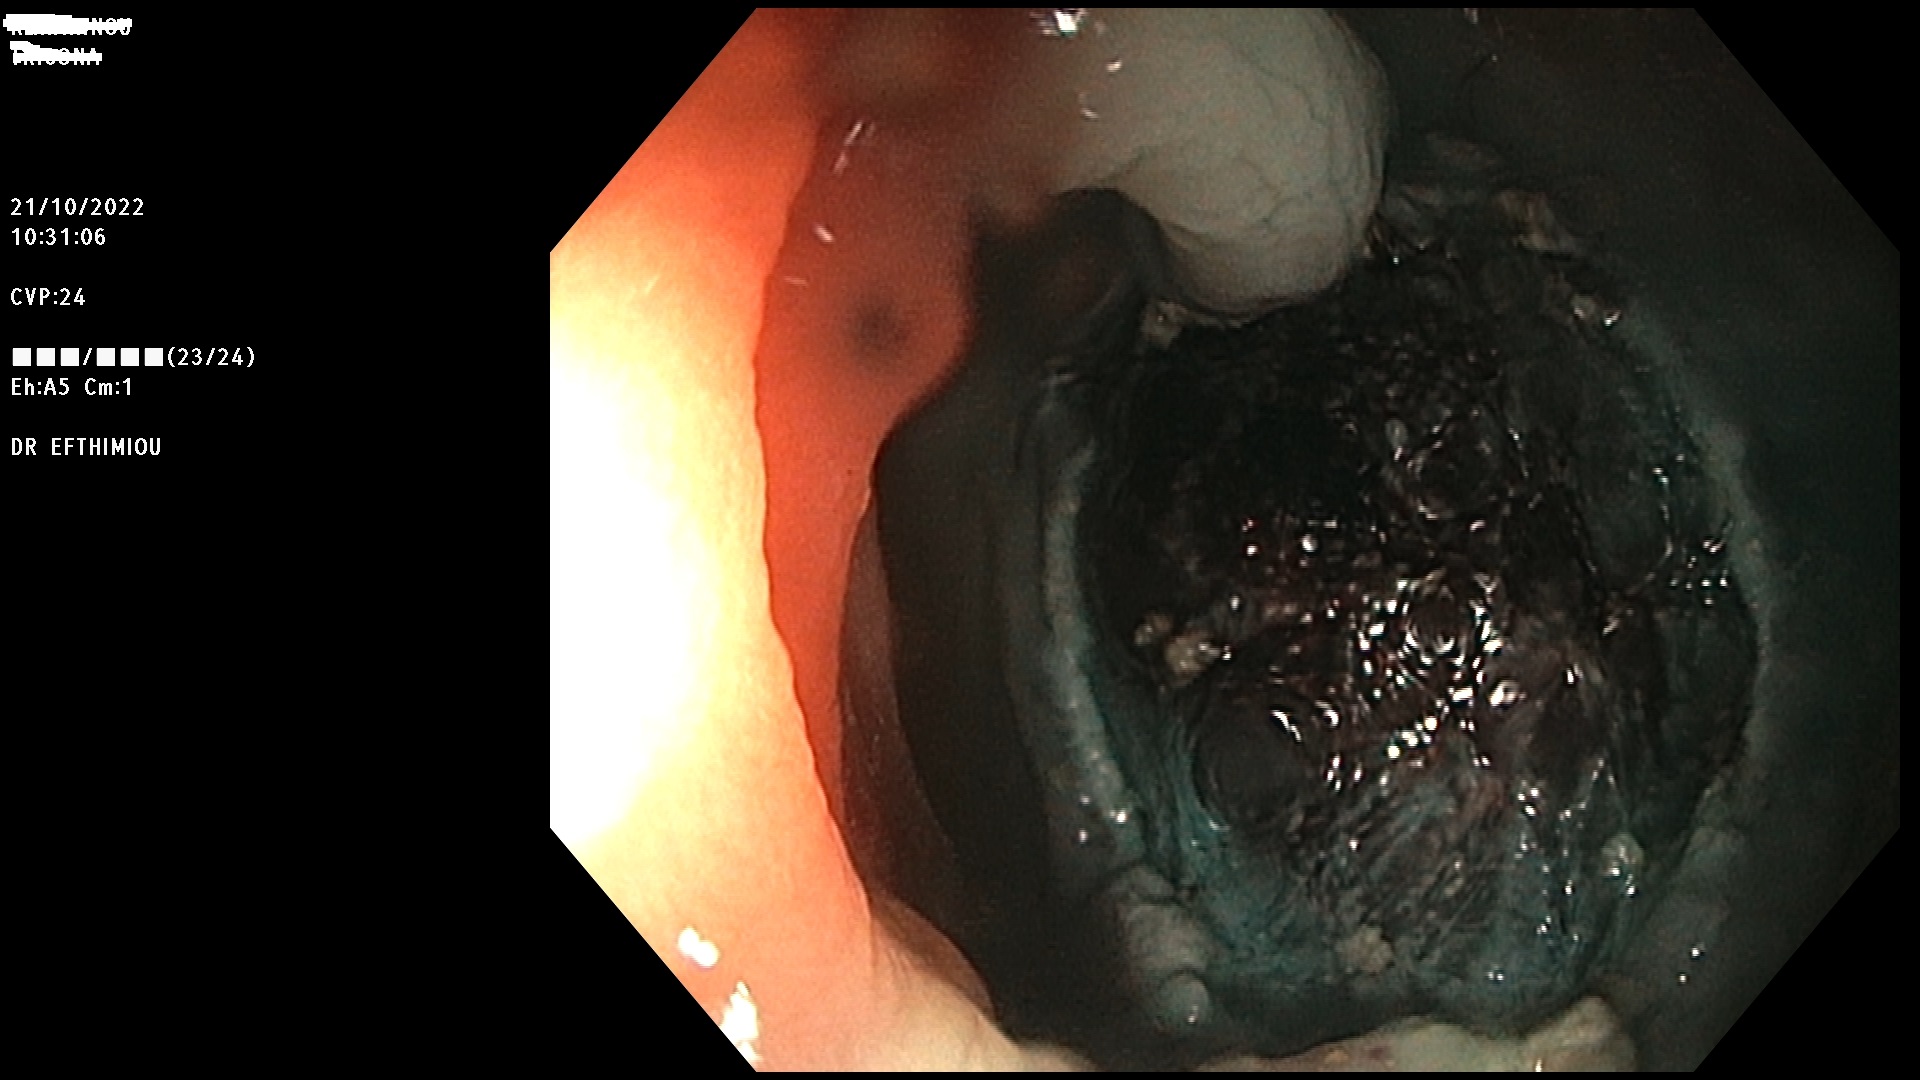

Η επέμβαση γίνεται κατά τη διάρκεια της κολονοσκόπησης με τη χρήση

διαφόρων εργαλείων (λαβίδες, βελόνες υποβλεννογόνιας έγχυσης, βρόχοι

διαθερμίας, ψυχροί βρόχοι, endoloops, κ.ά.) ανάλογα με το μέγεθος, τη

μορφολογία και την εντόπιση του πολύποδα (Εικόνες 1-3). Ο ασθενής

βρίσκεται σε ήπια καταστολή («μέθη») και δεν αισθάνεται καθόλου πόνο.